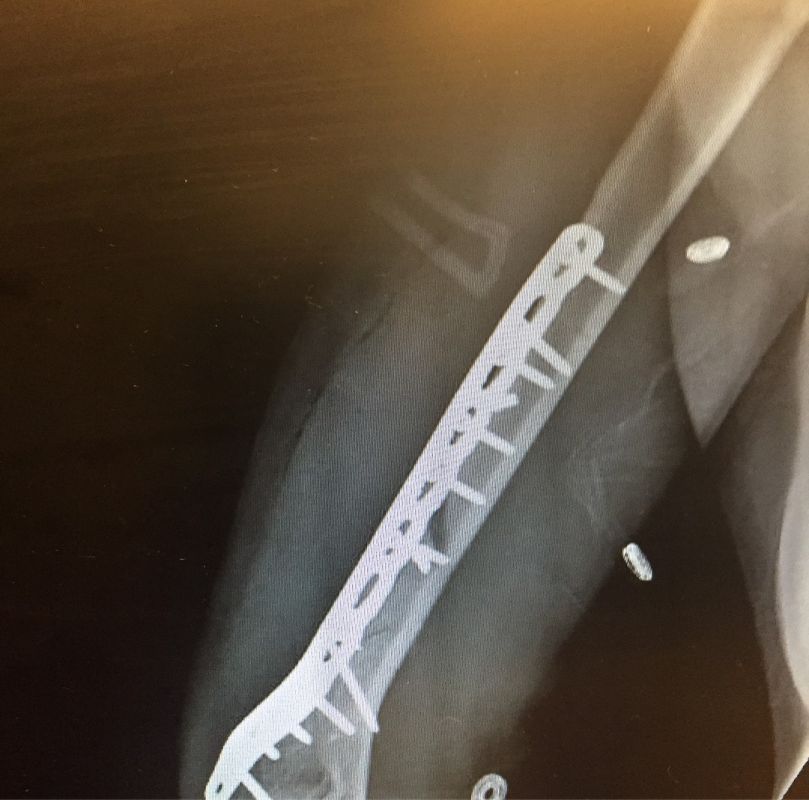

Pe contul său de Facebook, celebra schioară alpină americană Lindsey Vonn a postat imagini terifiante cu cele mai grave accidentări suferite de-a lungul carierei sale impresionante.

Alături, a inserat și un text sugestiv: „Reparaţii de menisc medial şi laterale, fracturi bilaterale ale platou genunchiului, fractură de humerus fracturat cu leziuni nervoase… Dacă n-aş avea voinţa de a continua să muncesc din greu, nu aș fi reușit niciodată. Înapoi la podiumul olimpic; indiferent ce obstacol vei înfrunta, poţi găsi întotdeauna o cale de a-l depăși”.